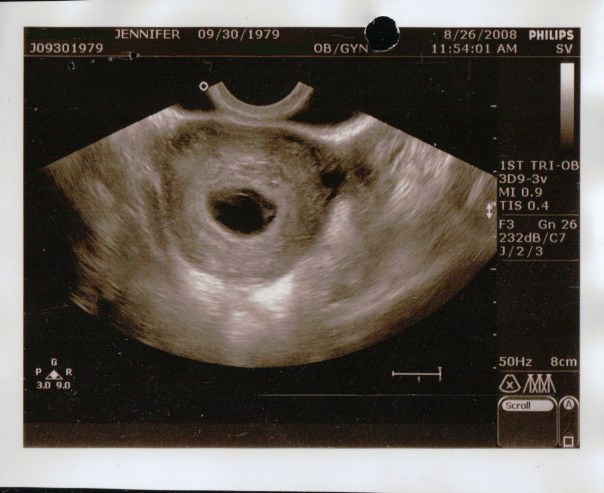

This image was during the transvaginal ultrasound, again the dark ovular hole in the center is the sac. I was supposed to be 11 weeks and 3 days along, but the sac was empty (blighted ovum 😦 ) and was measuring at only 6 weeks.

She had me go to the bathroom to empty completely. Woohoo! I was thrilled because I was so uncomfortable. I peed as much as I could but when she started to do the transvaginal ultrasound she said that my bladder was still too full and sent me to empty again. Okay. She tried the transvaginal ultrasound again, and she again mentioned that my bladder wasn’t empty, but it must’ve been ok because she continued the exam. I found the transvaginal ultrasound painful but I kept quiet through it. She was moving and twisting the wand in all sorts of directions. She didn’t say anything through the whole exam until towards the end when she said that she was coming back out, she mentioned that she took a look at the ovaries and she pointed out the sac again.

After a short while we were brought into a room with the same NP that I had for my first prenatal visit. First she asked about the bleeding which I explained to her. Then she told me “It looks like you’re having a miscarriage.” She said that the pregnancy hadn’t progressed since the last time that they saw me, that I was measuring at 6 weeks (when I should be almost 12), that the sac was misshapen and should be round (when the tech pointed out the sac we saw an oval shape), and this is called a blighted ovum when the sac grows, but the baby doesn’t. Then she said something about a “rod”, but my husband and I heard two different things. I thought I heard her say that “All we’re seeing is a rod when we should be seeing a baby by this point.” And my husband thought he heard her say that, “We’re not even seeing a rod when we should be seeing a baby by this point.”